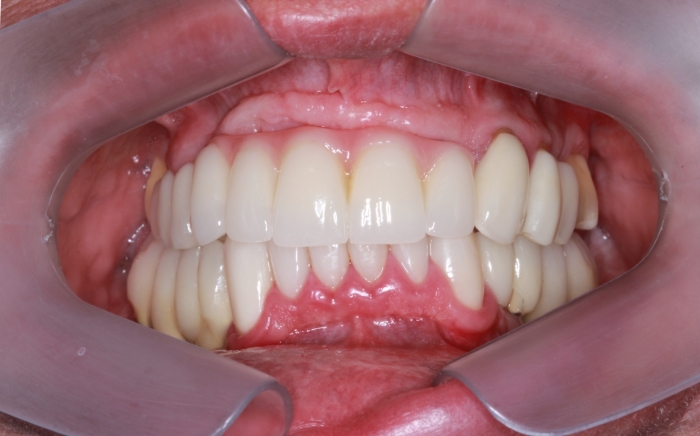

Próteses Fixas Definitivas Superior e Inferior em 2016 - Clínica Cliniface

Próteses Fixas Definitivas Superior e Inferior em 2016